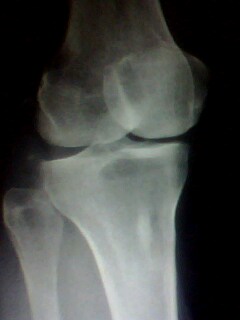

以下是引用muzi888在2010-5-12 11:02:00的发言:[br]骨岛,髁间棘及胫骨关节面有骨增生改变,余无异常。

以下是引用随光逐影在2010-5-12 14:43:00的发言:[br]1)胫骨上段骨岛。2)膝关节退行性改变。